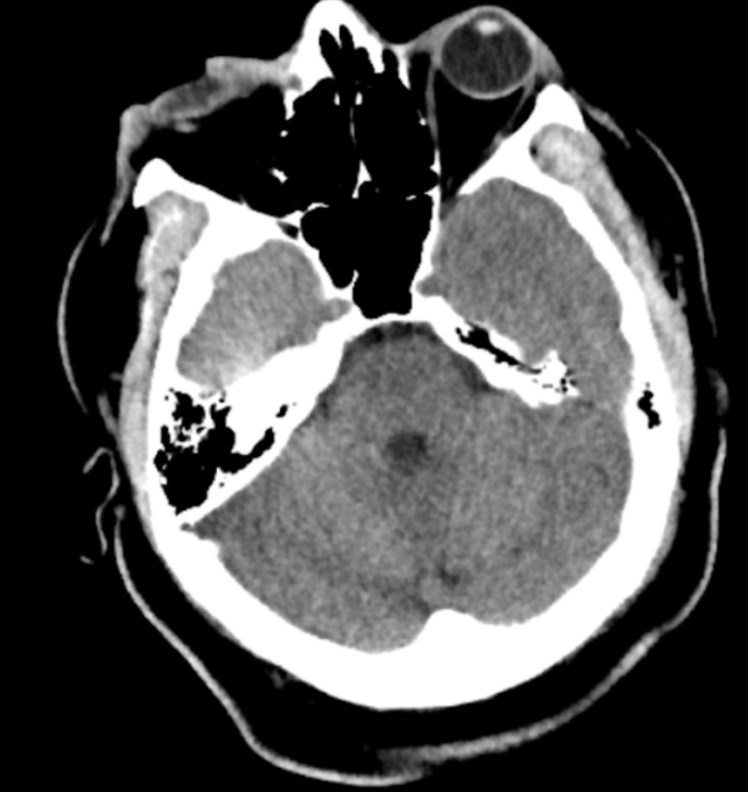

What’s the diagnosis? Gepost op 8 oktober 2018 door netwerkvsseh What’s the diagnosis? @emdaily.cooperhealth.org Dit delen: Delen op X (Opent in een nieuw venster) X Share op Facebook (Opent in een nieuw venster) Facebook Delen op LinkedIn (Opent in een nieuw venster) LinkedIn E-mail een link naar een vriend (Opent in een nieuw venster) E-mail Afdrukken (Opent in een nieuw venster) Print Vind-ik-leuk Aan het laden... Gerelateerd